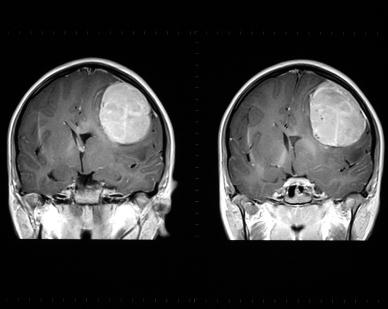

Современные исследования и методы диагностики играют важную роль в выявлении различных заболеваний. Особенно важны они в случаях, связанных с раком головного мозга. Это опасное заболевание занимает одно из первых мест среди онкологических патологий, и его обнаружение и выявление на ранней стадии является залогом успешного лечения.

| МРТ (магнитно-резонансная томография) | Визуализация структуры и состояния головного мозга |

Рак головного мозга – это опухоль или заболевание мозга, которое может быть сложно обнаружить из-за своего расположения. Для точного диагноза и плановых операций обычно требуется биопсия ткани мозга. Однако, в случае рака головного мозга, невозможно сделать биопсию на ранних стадиях заболевания. Поэтому общий анализ крови является ключевым методом исследования для раннего выявления патологий мозга.

Наличие определенных изменений в общем анализе крови может подсказывать врачу о необходимости дополнительных обследований, таких как компьютерная томография или магнитно-резонансная томография головы, для более точного определения диагноза и локализации опухоли.